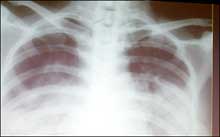

A chest X-ray of a SARS victim. Scientists conducting research in eastern China have found that a medicine used to treat schizophrenia is effective in treating patients with the deadly SARS disease.(AFP

This undated file photo shows a chest X-ray of a SARS victim. Scientists conducting research in eastern China have found that a medicine used to treat schizophrenia is effective in treating patients with the deadly SARS disease. [AFP]